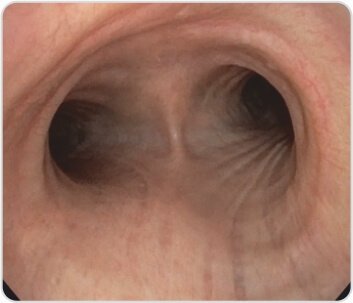

الشكل 1: الغشاء المخاطي الصحي